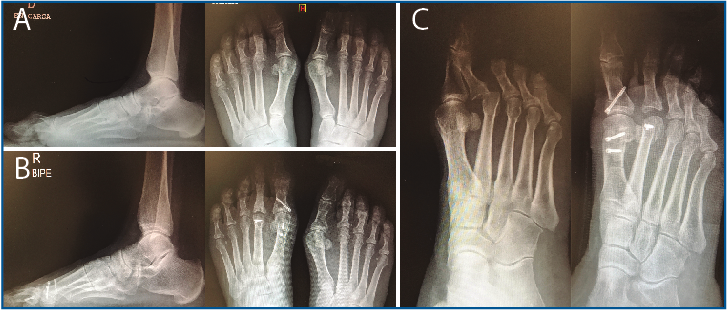

En la Figura 16A se muestra el estudio radiológico de frente y de perfil en carga preoperatorio y en la Figura 16B el control postoperatorio a los 6 meses de evolución con reducción de la articulación MTF.

En la Figura 16C puede verse la proyección oblicua pre- y postoperatoria a los 6 meses de evolución con buena reducción MTF.

Figura 16. A: estudio radiológico de frente y de perfil en carga preoperatorio evidenciando la luxación metatarsofalángica (MTF) asociada a garra interfalángica proximal (IFP) del 2.º dedo; B: control postoperatorio a los 6 meses de evolución con reducción de la articulación MTF; C: proyección oblicua pre- y postoperatoria a los 6 meses de evolución.